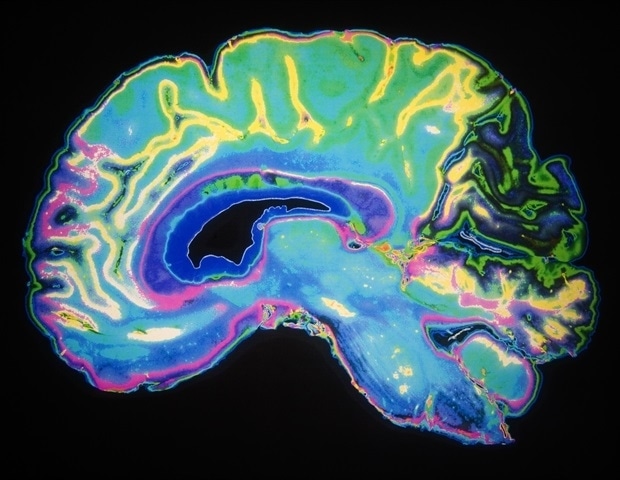

“We first took MRI scans of the participants when they were 73 years old. One of the most striking things about the study for me is how wide the differences are between their scans,” Cox wrote.

“Even though they were all the same age, some brains looked perfectly healthy (and wouldn’t be out of place amongst scans of 30 or 40 year olds),” he said. “Whereas others showed lots of shrinkage and damage to the white matter connections, along with other features that are related to cognitive ageing and dementia.”

White matter is the tissue that forms connections between brain cells and the rest of the nervous system, helping these regions communicate with each other through nerve signals. Having decreased or damaged white matter can slow the brain’s ability to process information.

Overall, “it shows us that brain ageing at age 73 is not an inevitability, while also strongly motivating us to research what we can do to emulate those lucky few who arrive at that age with such pristine brains,” Cox said.